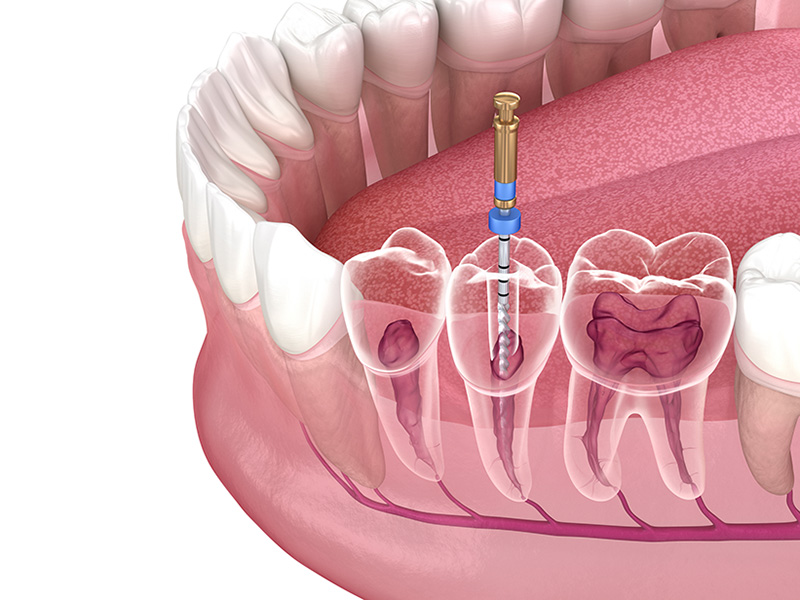

The Painless Root Canal Procedure

At theBest dental hospital in Pragathi Nagar we ensure that your root canal treatment is as comfortable and painless as possible. Here’s a step-by-step overview of the procedure:

1. Diagnosis and X-ray: Your dentist will examine the affected tooth and take an X-ray to assess the extent of the infection.

2. Anesthesia: Local anesthesia is administered to numb the tooth and surrounding area, ensuring a painless experience.

3. Pulp Removal: The infected or damaged pulp is carefully removed from the tooth.

4. Cleaning and Disinfection: The interior of the tooth is thoroughly cleaned and disinfected to remove all bacteria.

5. Filling: The cleaned root canals are filled with a biocompatible material and sealed to prevent further infection.

6. Restoration: A crown is usually placed on the treated tooth to restore its function and appearance.